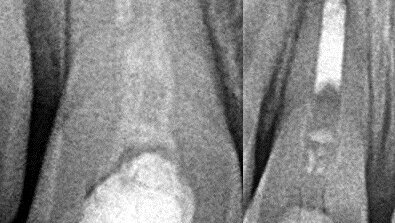

Slike 2a i 2b. Inicijalno kliničko stanje.

Jednog kišnog jutra zazvonio je telefon u mojoj privatnoj ordinaciji. Ordinirajući lekar bio je veoma nestrpljiv da zakaže što raniji termin za svog pacijenta, jer se radilo o slučaju povrede zuba kod osmogodišnjeg deteta. Devojčicu sam primio na pregled istog popodneva. Dva dana ranije, u saobraćajnoj nezgodi, malu Marlenu udario je automobil. Na desnom gornjem centralnom sekutiću bila je prisutna fraktura gleđi i dentina, dok je levi centralni sekutić bio utisnut u alveolarnu kost, intrudiran (slike 2a i 2b). Desni centralni sekutić reagovao je na termičke nadražaje i davao pozitivan rezultat na ispitivanje vitaliteta električnim testom. S druge strane, nije bilo moguće izvršiti ispitivanje vitaliteta na intrudiranom levom centralnom sekutiću.